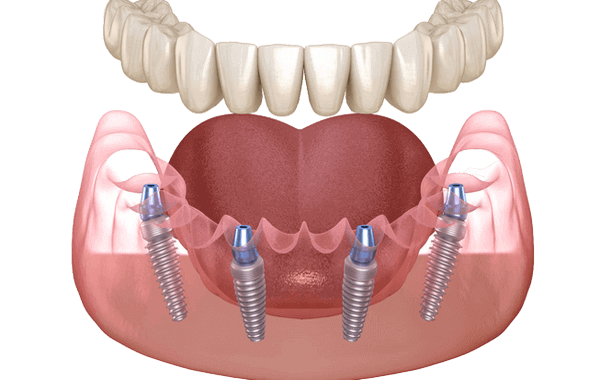

Ի՞ՆՉ Է All-ON-4 -Ը

Տեխնոլոգիայի էությունը արտացոլված է անվանման մեջ` այն բառացիորեն թարգմանվում է որպես «բոլորը չորսի վրա»: Ամբողջական ֆիքսված պրոթեզը ամրացվում է միայն չորս հենարանների՝ չորս ատամնաբուժական իմպլանտների վրա։

Իմպլանտները տեղադրվում են հատուկ ձևով՝ երկուսը՝ ուղղահայաց և, որպես կանոն, միմյանց զուգահեռ՝ առաջնային հատվածում։ Եվս երկուսը տեղադրվում են հեռավոր հատվածում՝ անկյան տակ, 5-6-րդ ատամների տեղում: Հեռավոր իմպլանտների թեք տեղը պատահական չի ընտրվել։ Սա մեծացնում է ոսկորների հետ շփման տարածքը, թույլ է տալիս օգտագործել դրա ավելի խորը և խիտ շերտերը, ինչպես նաև ընտրել այն հատվածները, որտեղ ծնոտի ոսկորն ավելի խիտ և ծավալային է: Բացի այդ, պրոթեզից բեռը բաշխվում է ավելի հավասարաչափ։

All-on-4-ը ամենաշատ ուսումնասիրված իմպլանտացիայի տեխնիկան է՝ պրոթեզի անմիջական բեռնումով: 1998 թվականին այն ներմուծել է պորտուգալացի բժիշկ Պաուլո Մալոն, ով առաջինն է բուժել 4 ատամնաբուժական իմպլանտներով և անմիջական պրոթեզով։ Այն բանից հետո, երբ Nobel Biocare-ը վերջնական տեսքի բերեց և բարելավեց տեխնոլոգիան՝ այն դուրս եկավ շուկա 2004 թվականին: